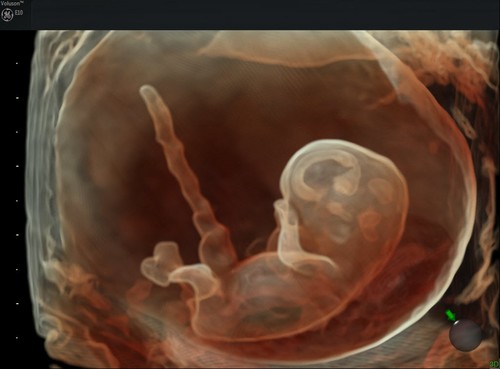

Пара «пузырьков» на снимке на самом деле являются беременностью двойней. Каждая из амниотических оболочек содержит эмбрион в возрасте 6 недель. Изображение вверху: четырехмерный ультразвуковой снимок лица плода в формате GIF.

Пара «пузырьков» на снимке на самом деле являются беременностью двойней. Каждая из амниотических оболочек содержит эмбрион в возрасте 6 недель. Изображение вверху: четырехмерный ультразвуковой снимок лица плода в формате GIF.Ученым потребовалось более столетия, чтобы объяснить таинственные результаты, полученные Спалланцани, и сконструировать аппарат, который, подобно гортани и ушам летучей мыши, генерирует неслышимый шум, а затем анализирует его эхо. Во время Первой мировой войны ВМС Великобритании использовали одну из первых рукотворных систем такого рода, чтобы обнаружить и потопить немецкую подводную лодку в Атлантическом океане. С тех пор эти системы далеко ушли вперед.

Другой снимок беременности двойней на сроке 8,5 недель.Сегодня одним из самых современных воплощений технологии являются ультразвуковые аппараты 4D. С их помощью можно долгое время наблюдать за плодом в животе матери с потрясающей четкостью в трех измерениях. «Раньше вы могли видеть только плоское двухмерное изображение плода в профиль, — говорит Барбара Дель Принс (Barbara Del Prince), главный управляющий директор по ультразвуковой продукции компании GE Healthcare. — Но сегодня вы можете наблюдать за его движениями в режиме 3D, видеть его улыбку или гримасу, рассмотреть его индивидуальные особенности».

Это изображение плода в возрасте 9 недель показывает развитие структур головного мозга.

Это изображение плода в возрасте 9 недель показывает развитие структур головного мозга.Родители любят просто разглядывать снимки, но врачи используют эту технологию для изучения органов и функций плода, таких как структура головного мозга (см. изображение выше) и работа сердца (изображение ниже).